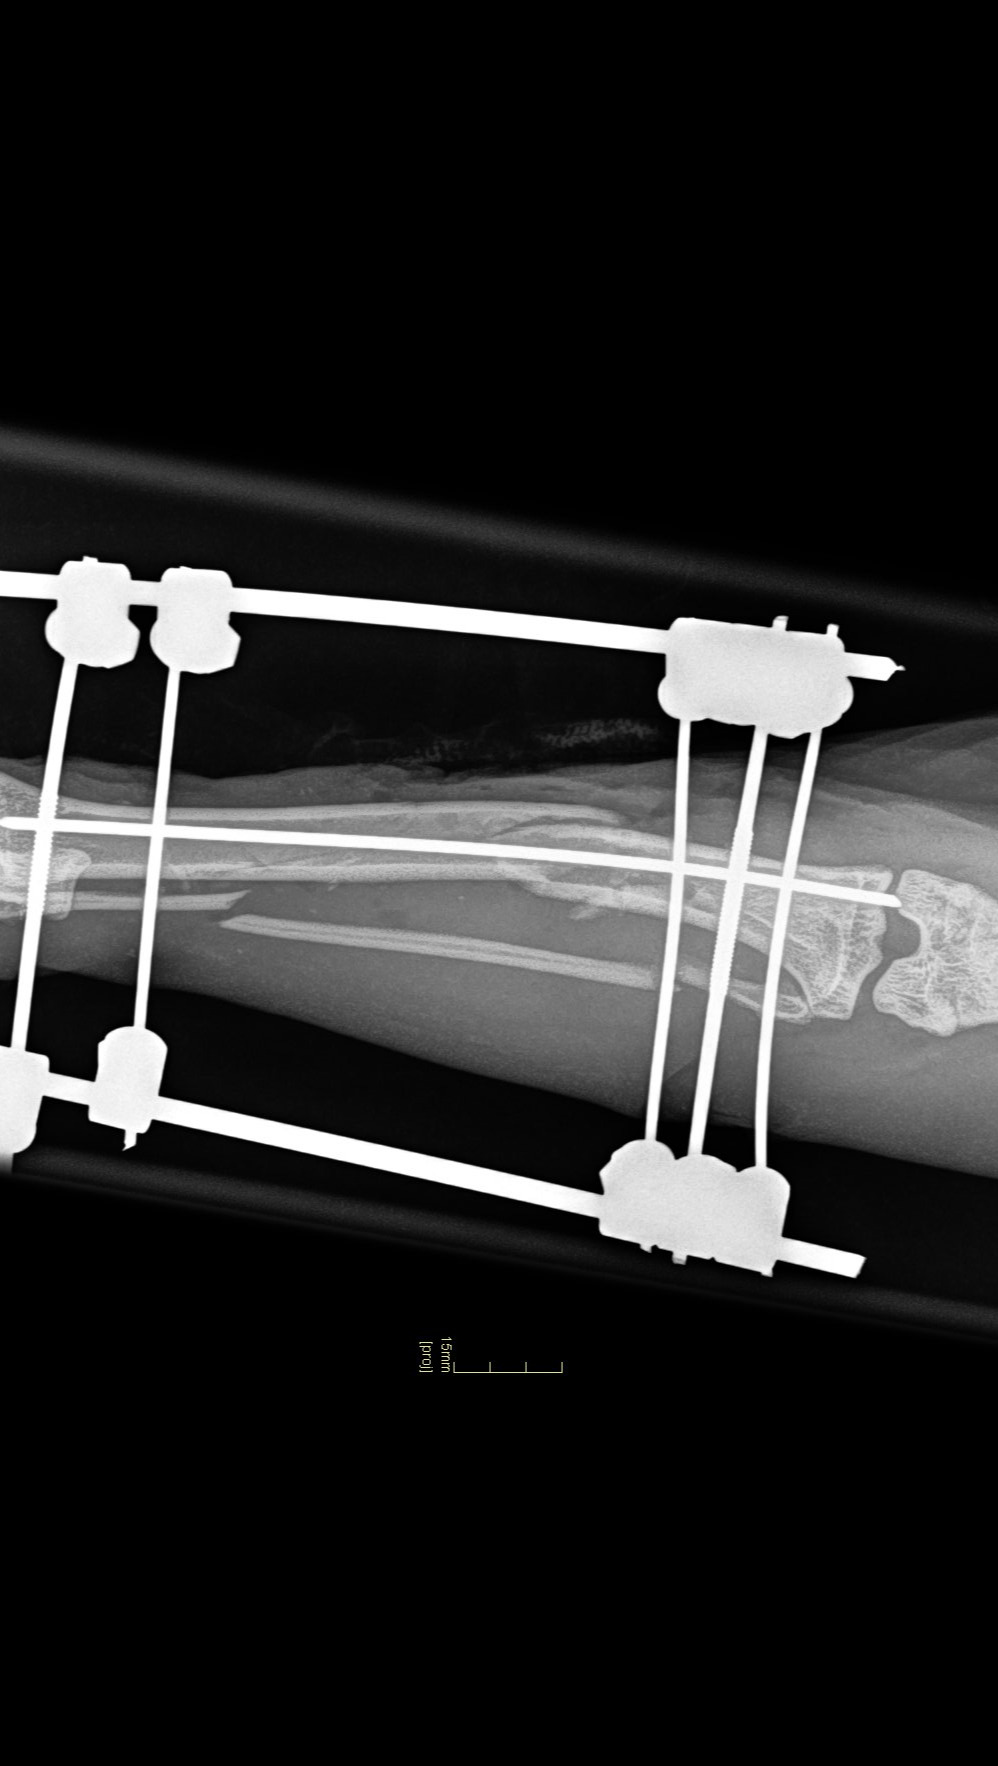

Inmiddels heeft hij deze operatie ondergaan en heeft nu een externe fixatie door zijn botten heen om het te laten genezen.

He has now undergone this surgery and now has an external fixation through his bones to allow it to heal.